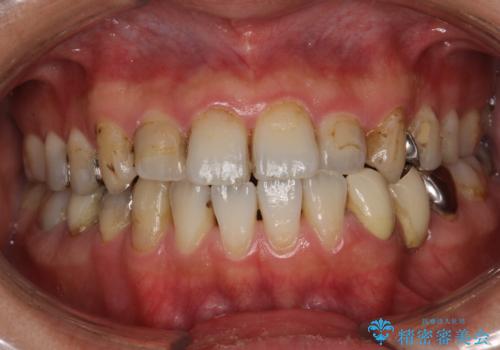

歯の表面に、茶色く色が残っている所がありますが、これは詰め物の変色の所と、虫歯になっている所です。以前に、CR(コンポジットレジン)による虫歯治療がされています。

CRは経年的劣化や、着色してしまうことがあります。PMTCでクリーニングを行うと、古いCRが目立つことがあるため、気になる際は詰め替えを行います。

茶色くなっている部分が、着色なのか、劣化なのか、虫歯によるものなのかは判別が難しいことがあります。そのため、定期的にPMTCを行うことで状態の確認が的確に行えます。

また、治療が開始される前などにも、全体的にクリーニングを行いご自身本来の歯の色、状態を精密に確認することが大切です。